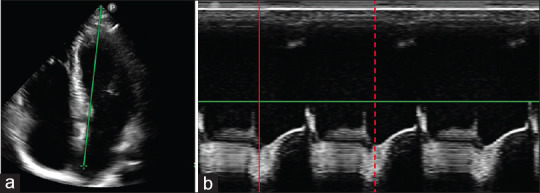

Methods: Twenty volunteers were scanned with HHE, standard echocardiography (SE), and CMR. LVEF and SV were measured with each modality, and their accuracy and precision were evaluated.

Abstract Image